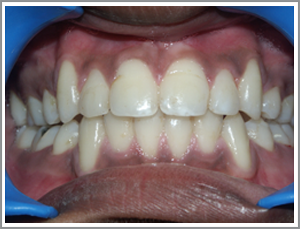

Before

After

ABC a 16 year old girl had a deep bite and upper teeth which were inclined backwards and irregular

( Angles Class 1 malocclusion )

Problem list : unsightly teeth and damage to the gums due to the deep bite.

Treatment plan : Non extraction - She was treated without removal of teeth by pushing the teeth out slightly (proclining ).

Treatment time : 12 months